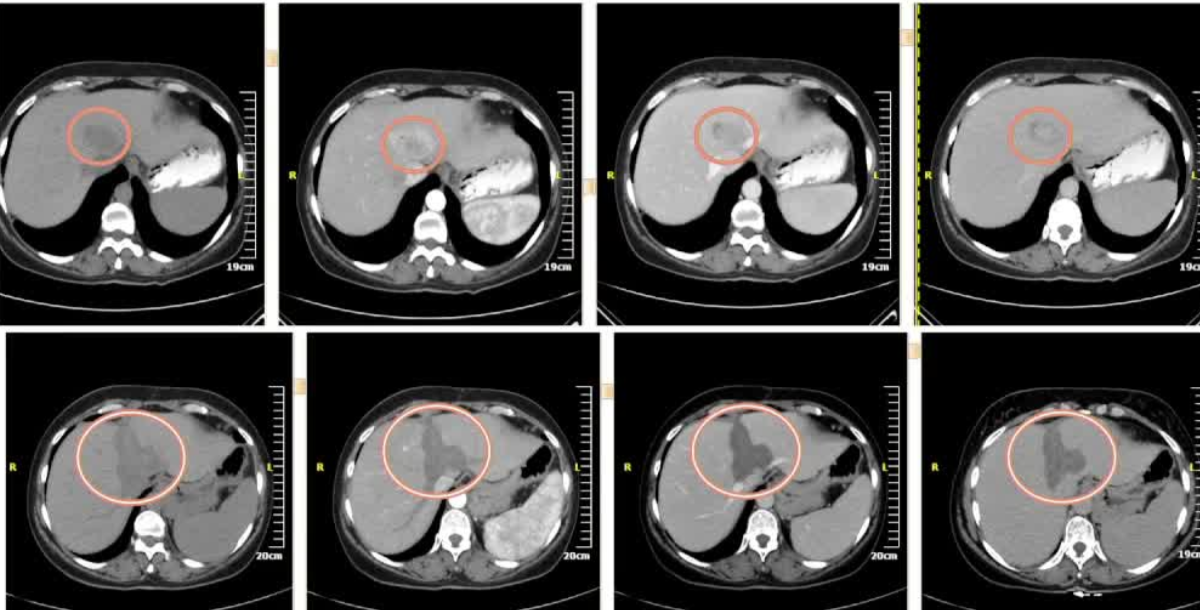

本文报道了一项多中心回顾性研究,探讨了在肝恶性肿瘤直径大于3厘米的患者中,结合使用球囊阻断微波消融(b-MWA)和球囊阻断经动脉化疗栓塞(b-TACE)的综合治疗方法。研究重点在于评估坏死区的外观和体积、安全性以及肿瘤学结果。

- 目标:报告在肝恶性肿瘤患者中使用b-MWA后继以b-TACE的多中心回顾性经验,重点关注坏死区的外观和体积、安全性和肿瘤学结果。

患者群体:共纳入23名患者,其中原发性肝癌(HCC)18例,肝内胆管癌(iCC)2例,转移性肿瘤(结直肠癌转移1例,肉瘤转移1例,乳腺癌转移1例)。

病变特征:最大平均直径为4.4厘米(±1厘米)。

治疗流程:采用单一步骤方法,先进行b-MWA,然后进行b-TACE(使用表柔比星或伊立替康)。

坏死区体积:平均坏死区体积为75立方厘米(±36),与供应商图表相比,坏死区体积增加中位数为103.2%(±99.8%)。

-

坏死区形状:22/23名患者(95.7%)的坏死区呈非球形。

并发症:无严重并发症发生,12/23名患者出现术后栓塞综合征。

完全缓解:1个月时为91.3%(21/23),3-6个月时为85.7%(18/21)。

部分缓解:1个月时为8.7%(2/23),3-6个月时为9.5%(2/21)。

疾病进展:3-6个月时,1/21名患者出现远处转移。

肿瘤体积减小:部分反应者的平均肿瘤体积减小率为78.8%(±9.8%)。

主要发现:b-MWA后继以b-TACE的单一步骤程序导致的坏死区体积大于供应商消融图表所建议的体积,且呈非球形,与消融期间阻断的血管段相吻合。